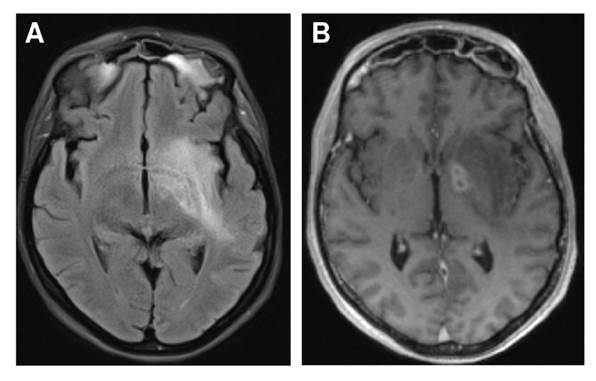

A pesar del manejo antibiótico, 10 días después del ingreso al hospital la paciente presentó hemiparesia izquierda, desviación de la comisura labial con parálisis facial central izquierda y disartria. Se practicó una nueva RM en la que se evidenciaron hallazgos de sinusitis fúngica invasiva con compromiso del espacio masticador, el cavum de Meckel, la fosa craneal media y la órbita izquierda; además, hubo signos de cerebritis y meningitis con trombosis del seno cavernoso izquierdo (figura 1).

Figura 1 Focos de cerebritis en el ganglio basal en secuencia FLAIR (A) y T1 después del contraste (B)